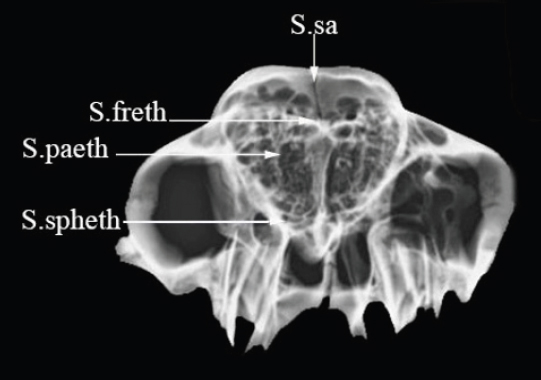

The inside a group

The skull sutures of this group are visible from the inside of the skull involving the ethmoid bone (Figs. 4 and 7). It articulates with the frontal bone dorsally, two parietal bones laterally, and sphenoid and vomer bone ventrally.

1. Sutura Serrata frontoethmoidalis (S.freth)

The suture is formed between the cribriform plate of the ethmoid bone and the ventral aspect of the frontal bone (Figs. 4a and 7b).

2. Sutura limbosa parieto ethmoidalis (S.paeth)

It is a bilateral and overlapping suture. It is located between the ethmoid bone's perpendicular plate and the medial wall of the parietal bone (Figs. 4b and 7c).

3. Sutura limbosa sphenoethmoidalis (S.spheth)

It is formed between the body of the presphenoid of the sphenoid bone and the perpendicular and cribriform plates of the ethmoidal bone (Figs. 4c and 7d).

Fig. 4. Vertical or inside view of skull showing the position of the skull sutures. (a) S.freth: Sutura frontoethmoidalis, (b) S.paeth: Sutura parieto ethmoidalis, (c) S.spheth: Sutura sphenoethmoidalis. The camel’s age is 6 months.